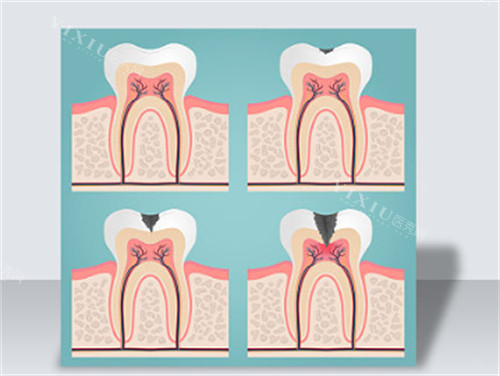

树脂补牙:220 元起 / 颗

根管治疗:根据治疗难度和牙齿位置而定

基础治疗项目价格相对较为稳定,但根管治疗会因牙齿情况不同而有差异。